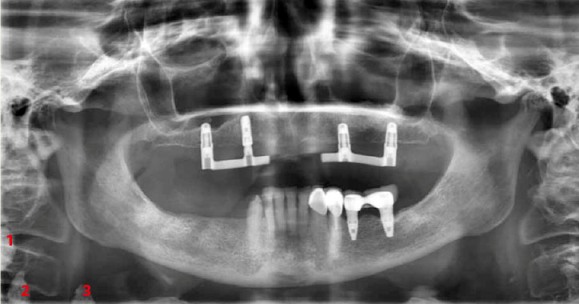

Op pagina 21 vroegen wij u naar de bijzonderheden op een postoperatieve panoramaopname (afbeelding 1 ) van een 77-jarige vrouwelijke patiënt.

Afb. 1

Panoramaopname uit oktober 2017.